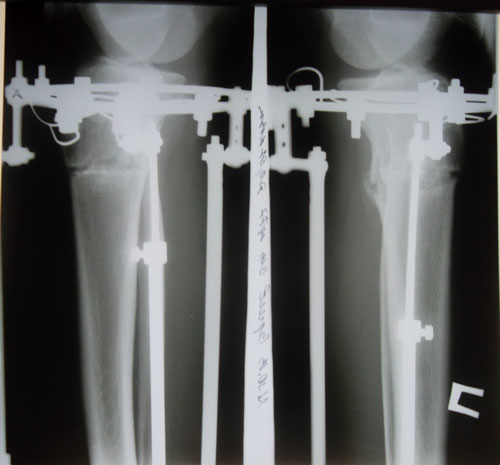

- Диагноз: О-образная деформация ног

Дата операции 20.08.2013г.

Дата снятия аппаратов 07.11.2013г.

Срок лечения 77 дней.